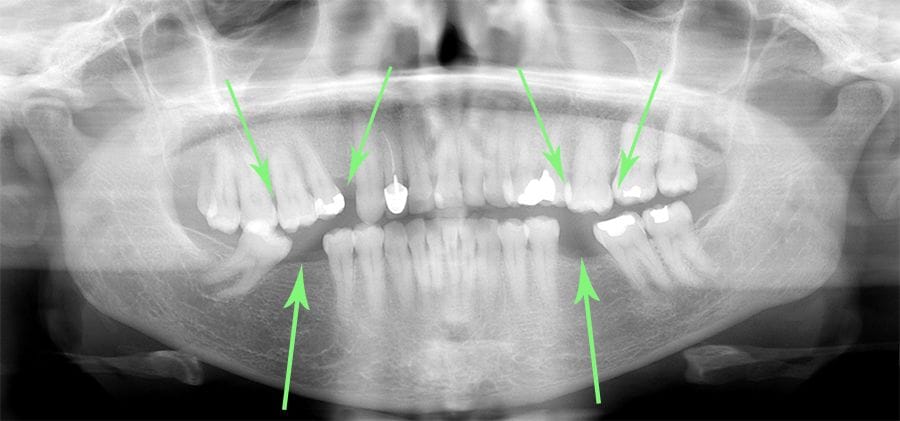

- Adjacent teeth started leaning in causing Gum problems

- Opposing tooth drifts downward

- The surrounding teeth all started moving

Overall Result: Entire area is malpositioned and more susceptible to tooth loss, gum disease and poor function.